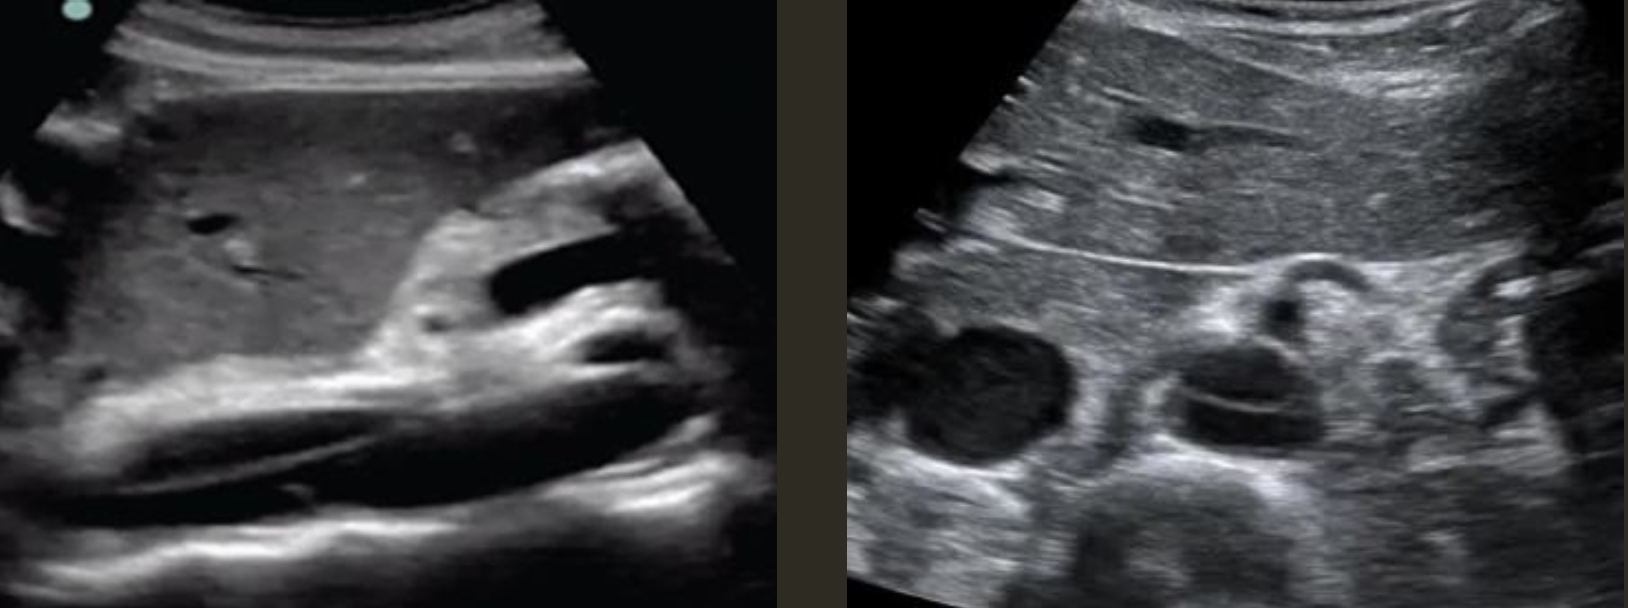

Aortic Dissection → intimal wall tears and allows blood flow between layers

2D US presentation: thin echogenic linear membrane fluttering in lumen creating a true and false lumen

color doppler: fill in both channels → pw shows regular flow in true and weak/no flow in false; asymmetrical kidney perfusion

DDX: AAA (focal dilation, no intimal flap)